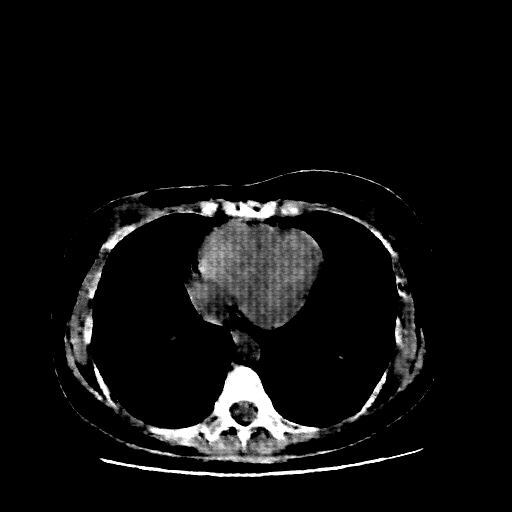

Generated VENOUS CT scan (A→B translation)

Full window (WL 1023.5, WW 4095 β†’ Low βˆ’1024, High +3071)

Actual HU range: [-1024.0, 892.4]